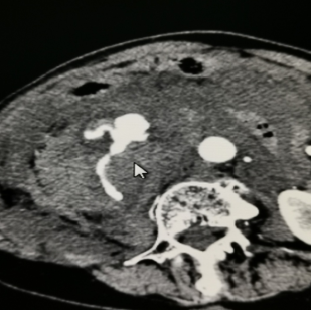

▲术中

右肾广泛活动性出血(不规则条带状、絮状低密度灶)